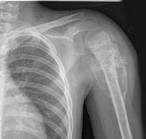

问题 男,28岁,右上臂肿胀、疼痛;无发热,无外伤史,请结合影像图像,选择最可能诊断()

选项 A.骨肉瘤 B.成骨性骨转移瘤 C.化脓性骨髓炎 D.滑膜肉瘤 E.骨巨细胞瘤

答案 A